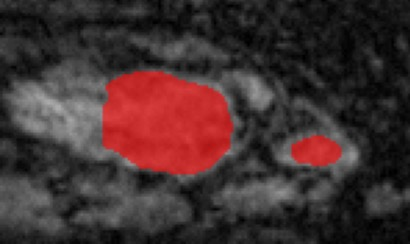

Medical data often exhibits long-tail distributions with heavy class imbalance, which naturally leads to difficulty in classifying the minority classes (i.e., boundary regions or rare objects). Recent work has significantly improved semi-supervised medical image segmentation in long-tailed scenarios by equipping them with unsupervised contrastive criteria. However, it remains unclear how well they will perform in the labeled portion of data where class distribution is also highly imbalanced. In this work, we present ACTION++, an improved contrastive learning framework with adaptive anatomical contrast for semi-supervised medical segmentation. Specifically, we propose an adaptive supervised contrastive loss, where we first compute the optimal locations of class centers uniformly distributed on the embedding space (i.e., off-line), and then perform online contrastive matching training by encouraging different class features to adaptively match these distinct and uniformly distributed class centers. Moreover, we argue that blindly adopting a constant temperature $\tau$ in the contrastive loss on long-tailed medical data is not optimal, and propose to use a dynamic $\tau$ via a simple cosine schedule to yield better separation between majority and minority classes. Empirically, we evaluate ACTION++ on ACDC and LA benchmarks and show that it achieves state-of-the-art across two semi-supervised settings. Theoretically, we analyze the performance of adaptive anatomical contrast and confirm its superiority in label efficiency.

翻译:医学数据经常呈现长尾分布和重度类别不平衡,这自然导致在对少数类别(即边界区域或罕见目标)进行分类时出现困难。最近的研究在长尾情况下通过装备医学影像的无监督对比标准,明显改进了半监督医学图像分割。然而,在标记的数据部分中,类别分布也极为不平衡,因此它们的表现如何仍不清楚。在本研究中,我们介绍一种采用自适应解剖对比度改进的对半监督医学分割行动的框架(ACTION++)。具体来说,我们提出了一种自适应监督对比损失,它首先在嵌入空间上计算出不同类别的优化位置(即离线),然后通过鼓励不同类别之间的特征与这些不同和均匀分布的类别中心相适应的在线对比匹配训练来进行自适应匹配。此外,我们认为,在长尾医疗数据中盲目采用常温度$\tau$不是最优的,因此通过一个简单的余弦计划来使用动态$\tau$来产生更好的多数类别和少数类别之间的分离。在实证方面,我们在ACDC和LA基准测试中评估ACTION++,并展示了其在两种半监督设置下的最新成果。从理论上讲,我们分析了自适应解剖对比度的性能,并证实了它在标签效率上的优越性。